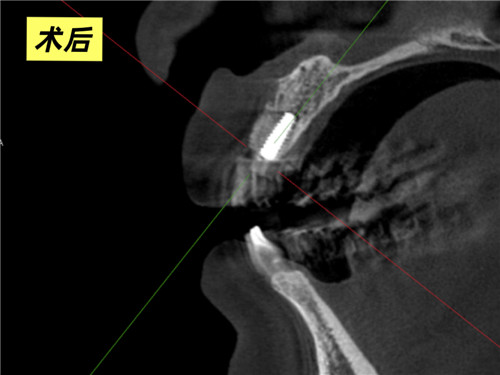

口腔科主任牛躍、副主任醫(yī)師鮑磊接診后,為其完善術(shù)前CBCT(口腔頜面錐形束CT)檢查,細(xì)致評(píng)估口腔條件,發(fā)現(xiàn)患者牙槽骨吸收嚴(yán)重,骨厚度僅4mm,術(shù)中需要植入人工骨粉。在征得患者同意后,科室團(tuán)隊(duì)精準(zhǔn)操作,術(shù)中植入骨粉并覆蓋骨膜,僅用30分鐘便成功完成手術(shù)。3個(gè)月后復(fù)查CBCT,植體與周圍骨質(zhì)結(jié)合良好,科室團(tuán)隊(duì)行牙冠修復(fù)后,患者對(duì)最終效果非常滿意,重新綻放自信笑容。